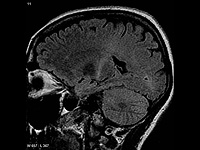

Wikipedia.org. Фото: Frank Gaillard

Исследователи из Тель-Авивского университета открыли молекулярный механизм развития бокового амиотрофического склероза и разработали РНК-терапию, потенциально способную остановить болезнь.

Боковой амиотрофического склероз (БАС) – неизлечимое нейродегенеративное заболевание, от которого страдают миллионы людей по всему миру. Этим заболеванием страдал знаменитый физик Стивен Хокинг. Он прожил с этой болезнью 50 лет и стал удивительным исключением: обычно пациенты, страдающие БАС, живут 3-5 лет.